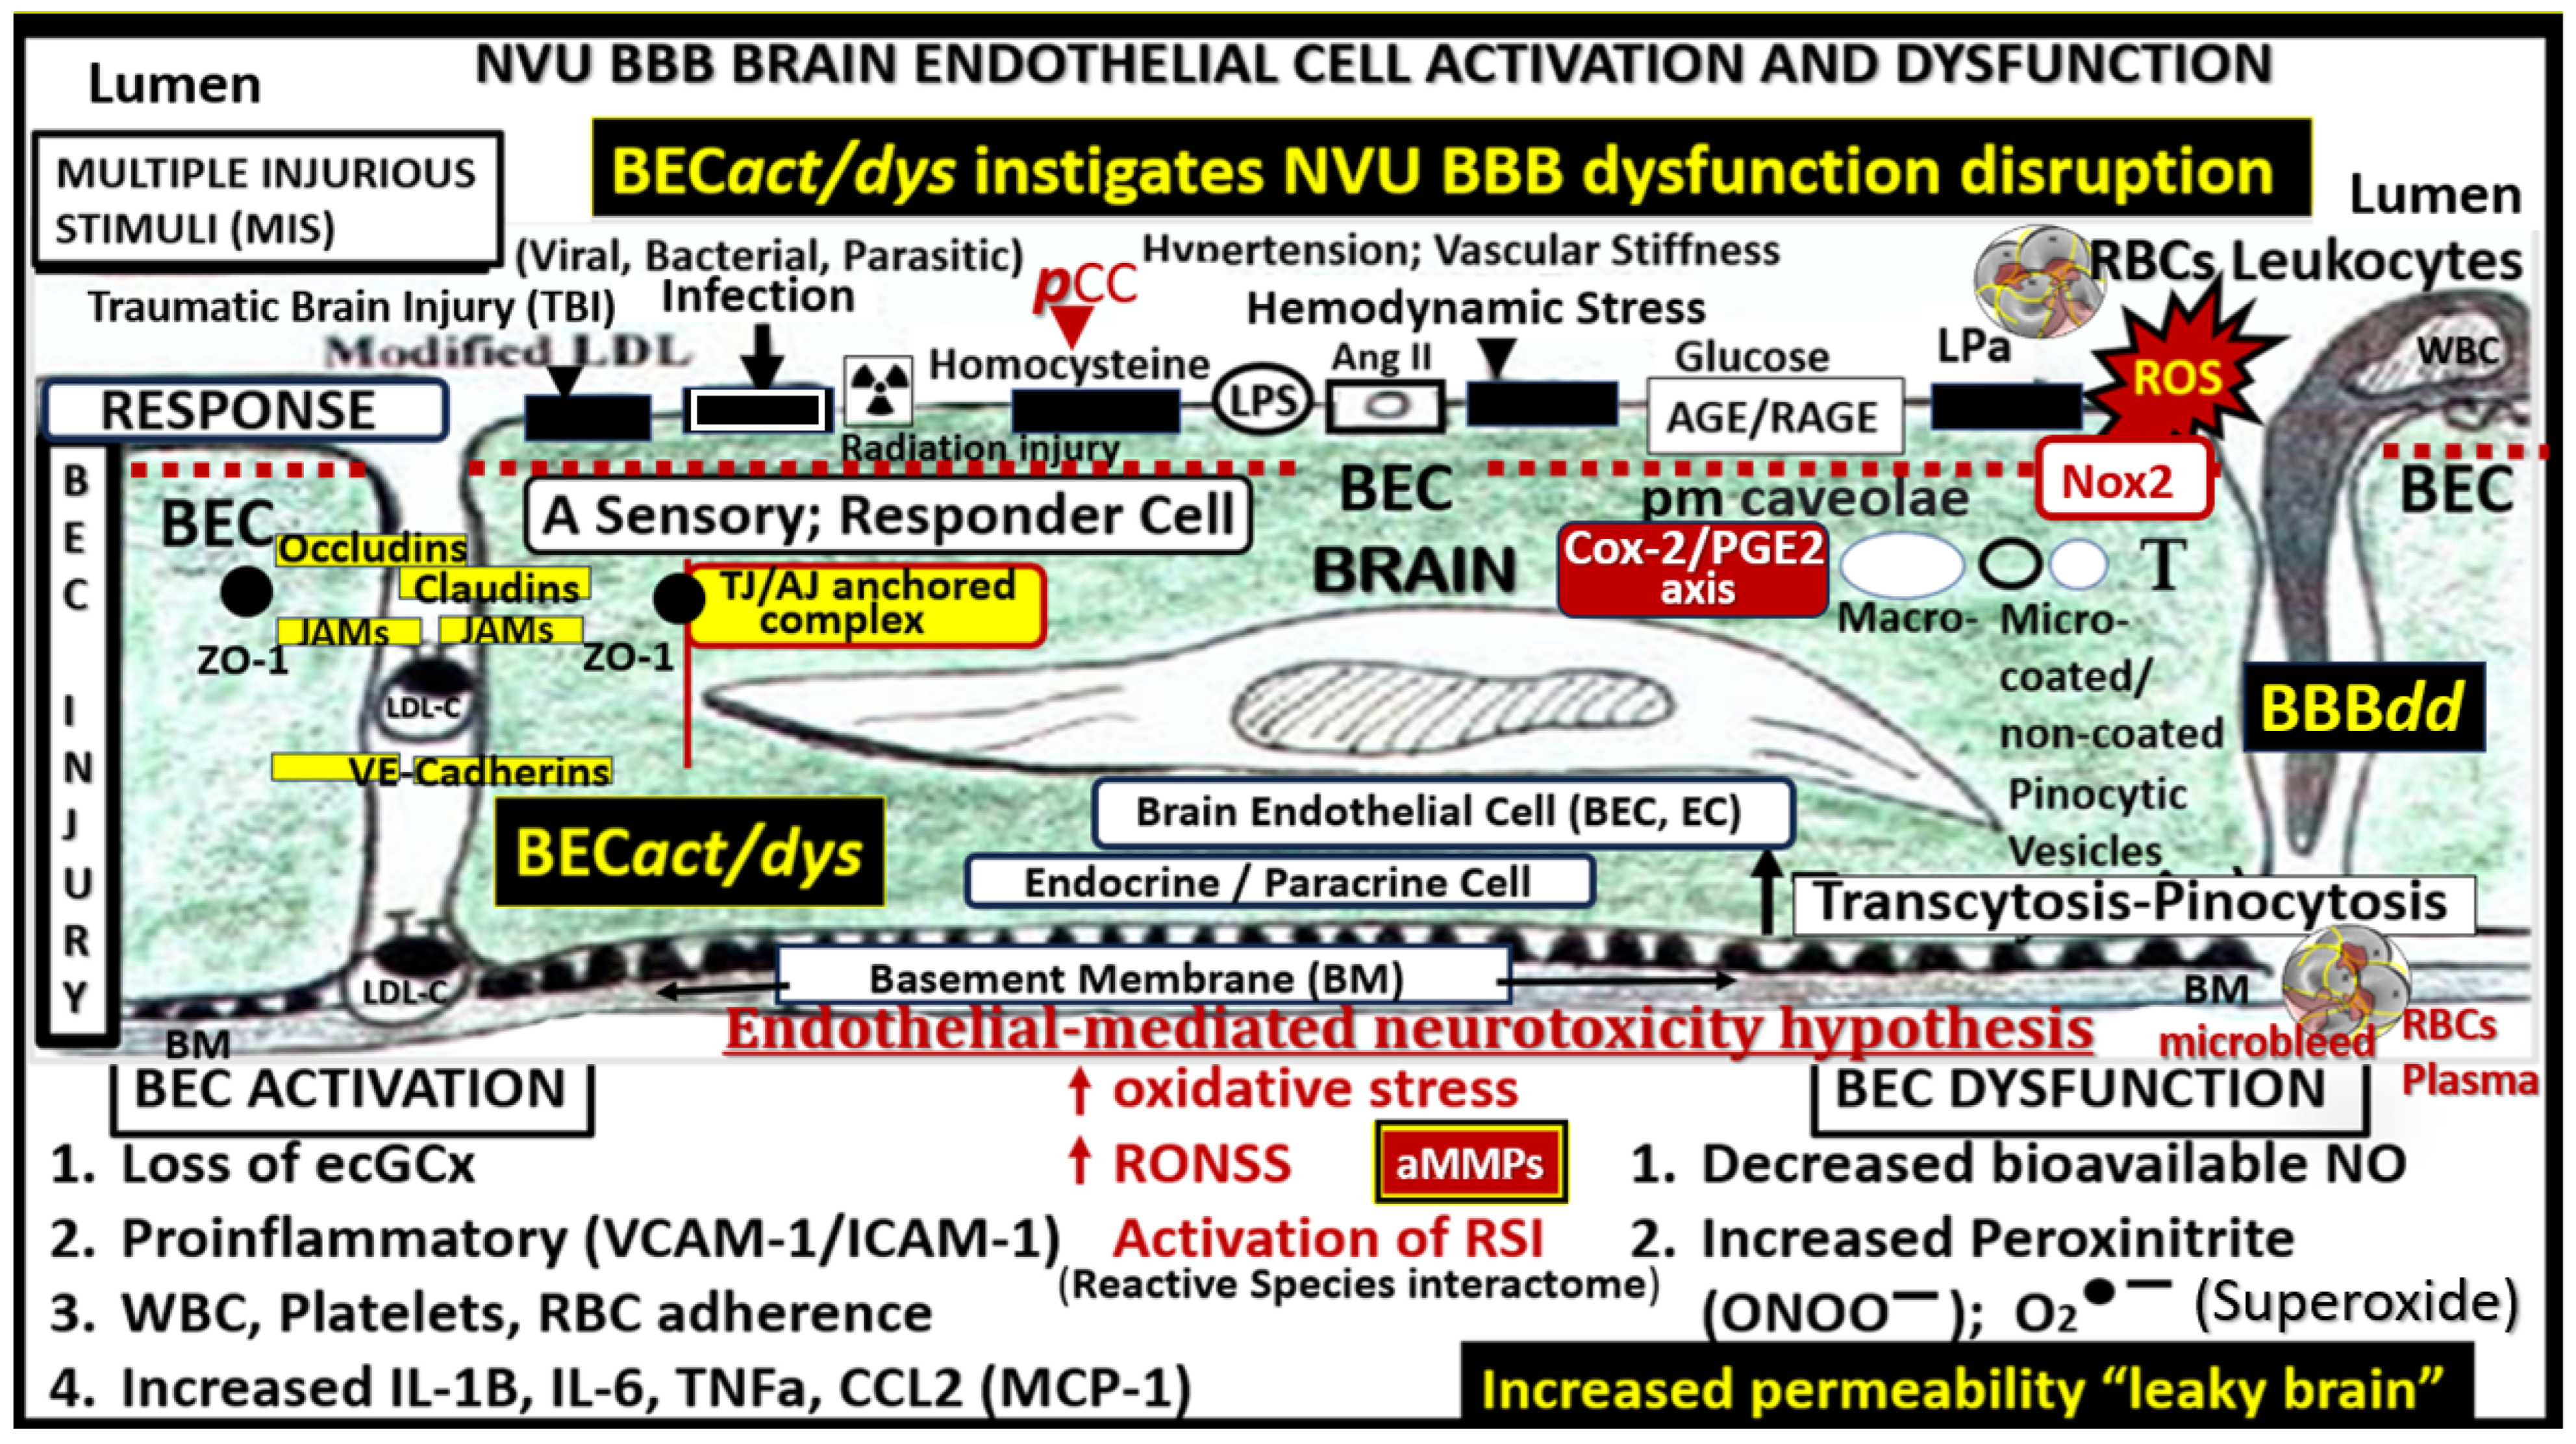

2.1. Brain Endothelial Cell Activation and Dysfunction (BECact/dys)

2.2. Blood–Brain Barrier Dysfunction and/or Disruption (BBBdd) with Increased Permeability